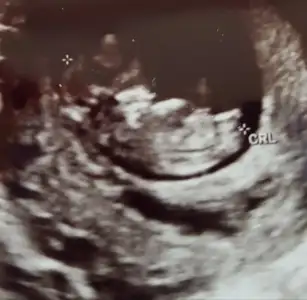

Evet cnm dogruydu kızım olucak insallahKız yorumlamıştım ögrendinizmi![]()

Siz bu işte uzmanlaşmısınız helal olsunKız yorumlamıştım ögrendinizmi![]()

Kız sanki başka usg varmı 11+ yada 12+ olmalı100 de 100 kızım diye bağırıyor dimi kizlar:) yanılıyor muyum?11+1

Şimdilik kız diyorumÇelişkide mi kaldınız? Sizin yorumunuz benim için önemli.. Yok başka fotosu bi bu var. Zaten daha12 haftalık olmadi

Ayy Allahım bana da nasip etsin böyle usg kız100 de 100 kızım diye bağırıyor dimi kizlar:) yanılıyor muyum?11+1